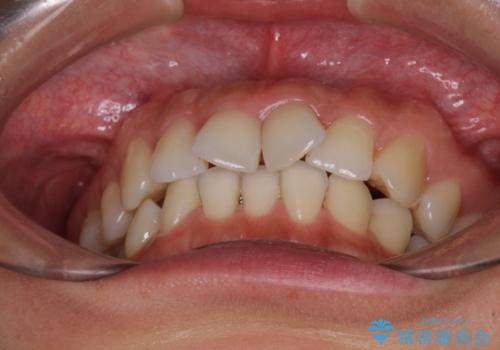

捻れた前歯をインビザラインで整える

- 捻れた前歯が飛び出しており、口が閉じにくいとのことで来院された患者様です。

出っ歯というわけではないものの、前歯の捻転により口唇が押し出されている状態でした。

親知らずを抜去し、歯列全体を後方に移動させつつ、IPR(歯と歯の間を削る)でスペースを獲得し、インビザラインを用いて叢生を解消しながら前歯の突出を改善することとしました。